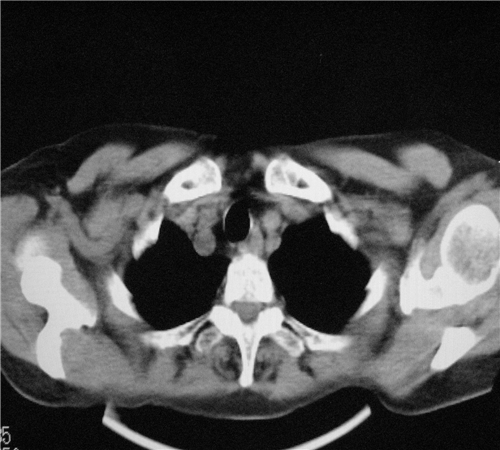

标题: CT26849:女67岁反复胸痛两天余,临床考虑夹层。

升主动脉增宽是怎么回事啊!食管有事吗?老师

1. 感染性病变,2.未见夹层,3.食道未见异常。

双下肺感染,右侧显著。有无夹层,增强扫描后再诊断。食道未见异常。

平扫未见确切夹层征,建议必要时增强扫描或mri检查。